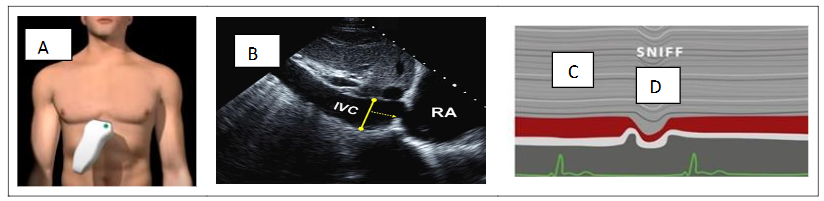

An assumed RAP is routinely added to the TR to estimate the sPAP. RAP pressure estimation is based on inferior vena cava (IVC) diameter in the subcostal view during quiet respiration and after “sniff” maneuver. The subcostal view is most useful for imaging the IVC, with the IVC viewed in its long axis.

The measurement of the IVC diameter should be made at end-expiration and just proximal to the junction of the hepatic veins that lie approximately 0.5 to 3.0 cm proximal to the ostium of the right atrium. To accurately assess IVC collapse, the change in diameter of the IVC with a sniff and also with quiet respiration should be measured, ensuring that the change in diameter does not reflect a translation of the IVC into another plane.

The measurements are done at end-diastole (figure 2).

IVC diameter ≤ 2.1 cm that collapses > 50% with a sniff suggests a normal RAP of 3 mmHg (range, 0–5 mmHg).

IVC diameter > 2.1 cm that collapses < 50% with a sniff suggests a high RAP of 15 mmHg (range, 10–20 mmHg).

In indeterminate cases in which the IVC diameter and collapse do not fit this paradigm, an intermediate value of 8 mmHg (range, 5–10 mmHg) may be used.

Figure 2. RAP estimation based on inferior vena cava (IVC) diameter in the subcostal view (A–B) during quiet respiration (C) and after “sniff” maneuver (D).